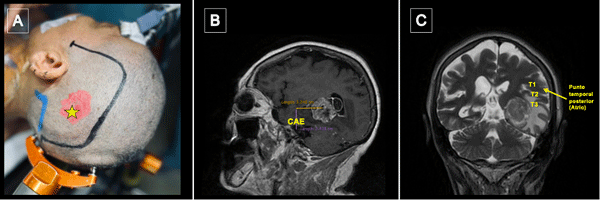

Figura 3.Punto temporal posterior, posicionamiento. A) Posicionamiento de la cabeza del paciente en cabezal de Mayfield Marcación de incisión centrada en punto temporal posterior (estrella amarilla). B) Se toma como referencia anatómica el conducto auditivo externo (CAE) para medición de punto temporal posterior. C) El punto temporal posterior corresponde topográficamente con el atrio del ventrículo lateral.

Figura 4. Ecografía intraoperatoria y mapeo cortical. A) Utilización de guía ecográfica intraoperatoria para identificar tumor y delimitar sus márgenes (A: Anterior; L: Lateral; M: Medial, P: Posterior). B) Marcación de los límites del tumor con tags de letras (A: Anterior; B: Medial; C: Posterior; D: Inferior) y de las áreas de mapeo positivo con presentación de anomia con dos tags de boca en región posterior de T2. Se expusieron también los giros temporales superior (T1), medio (T2) e inferior (T3) y se optó por corticotomía trans-T2.